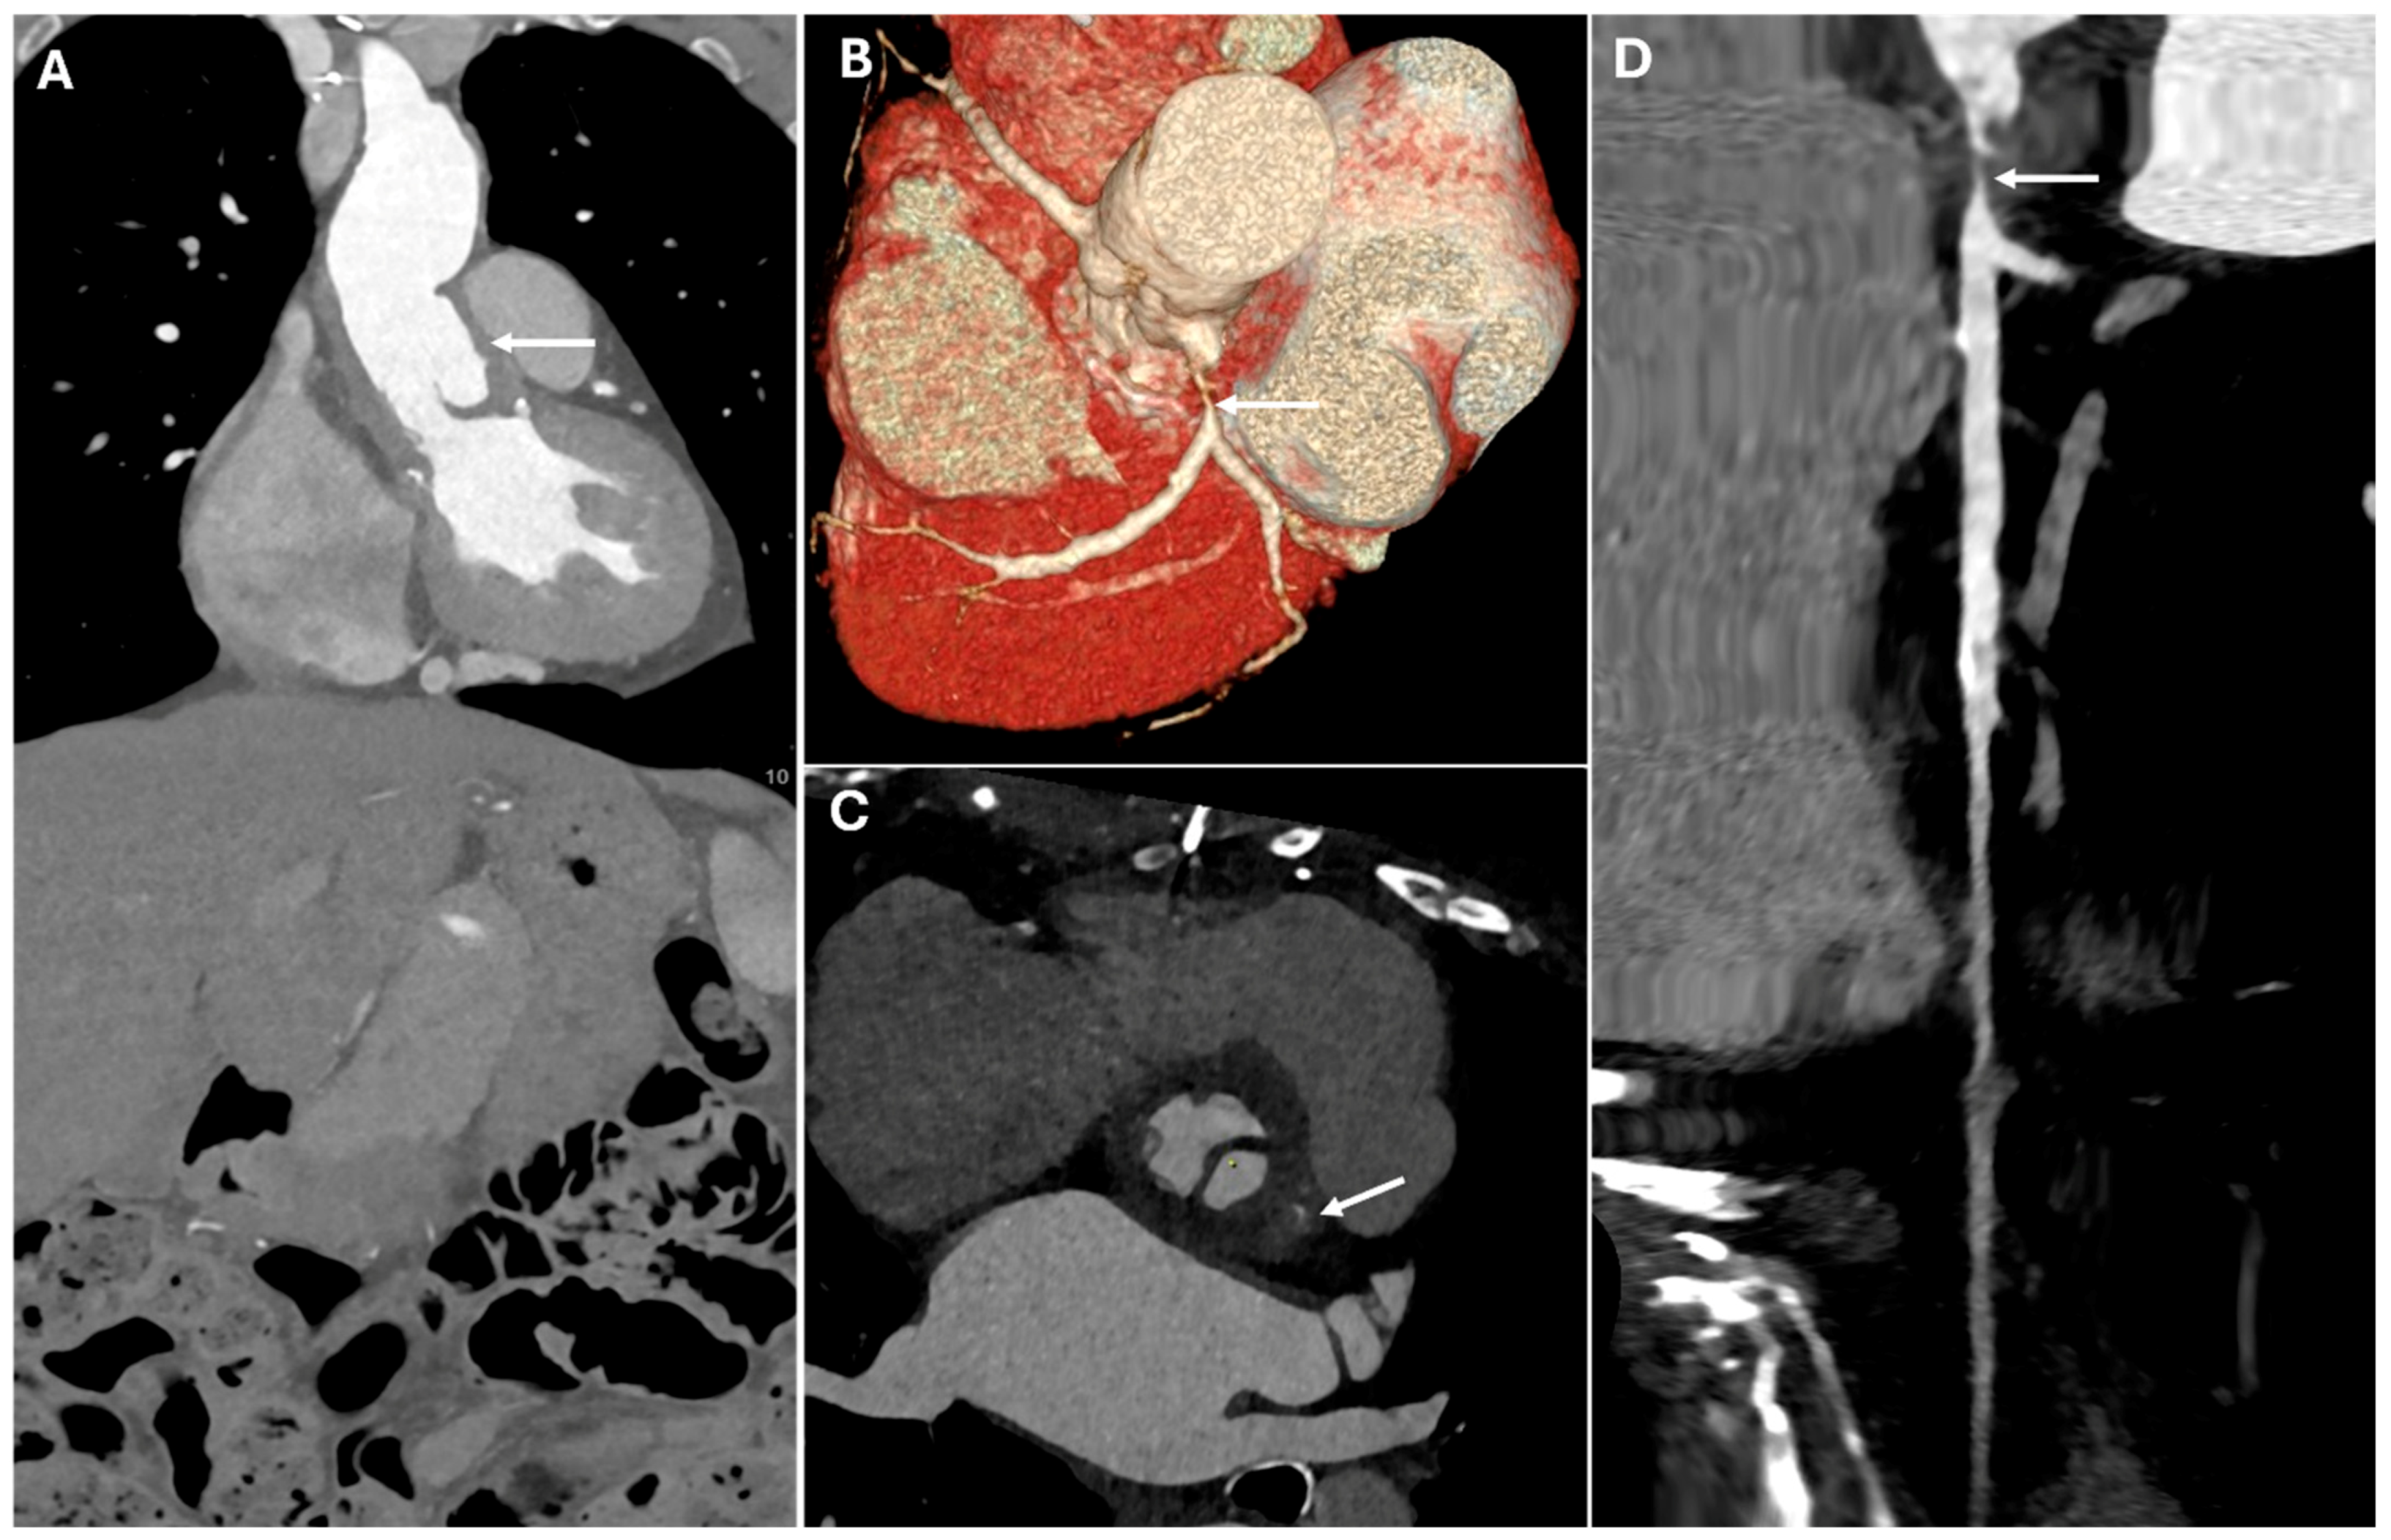

| Bentall Procedure | Aortic root aneurysms, Type A dissection | Composite graft with valve, coronary reimplantation | Tubular graft replacing aortic root, prosthetic valve |

| Cabrol Procedure | Complex reoperations, severe atherosclerosis | Prosthetic conduit for coronary artery reimplantation | Graft with parallel interposed conduit |

| Coronary Artery Complications | Coronary ostial obstruction | Narrowed or occluded ostium, diminished contrast opacification | Can lead to myocardial infarction |

| Graft Dehiscence and Leaks | Poor anastomotic integrity, infection, mechanical stress | Contrast extravasation at anastomotic sites, widened mediastinum, disrupted graft margins | Massive hemorrhage |

| Pseudoaneurysm | Suture failure, infection, chronic mechanical stress | Contrast-filled sac adjacent to graft, narrow neck | High rupture risk |

| Coronary reimplantation site | Well-positioned, opacified coronaries | Focal stenosis, absent enhancement, infarct signs |